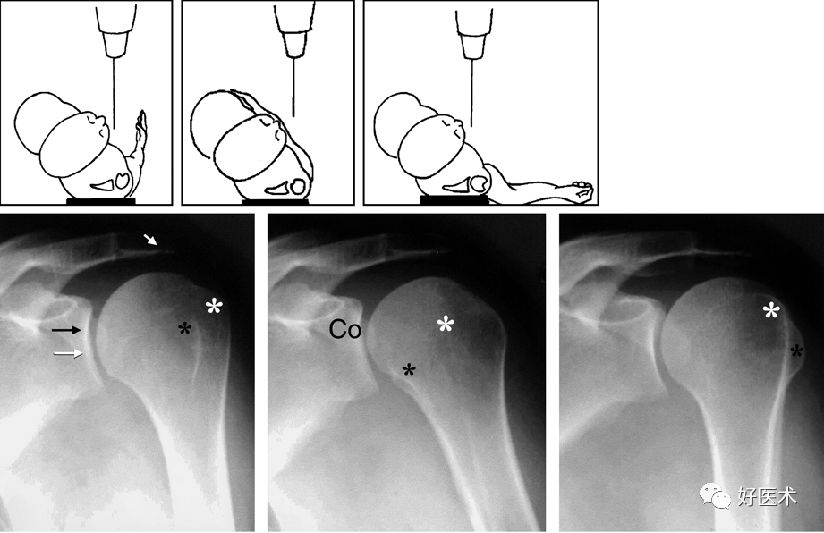

肩关节切线位

肩关节出口位

肩关节腋窝位

肩关节顶斜位